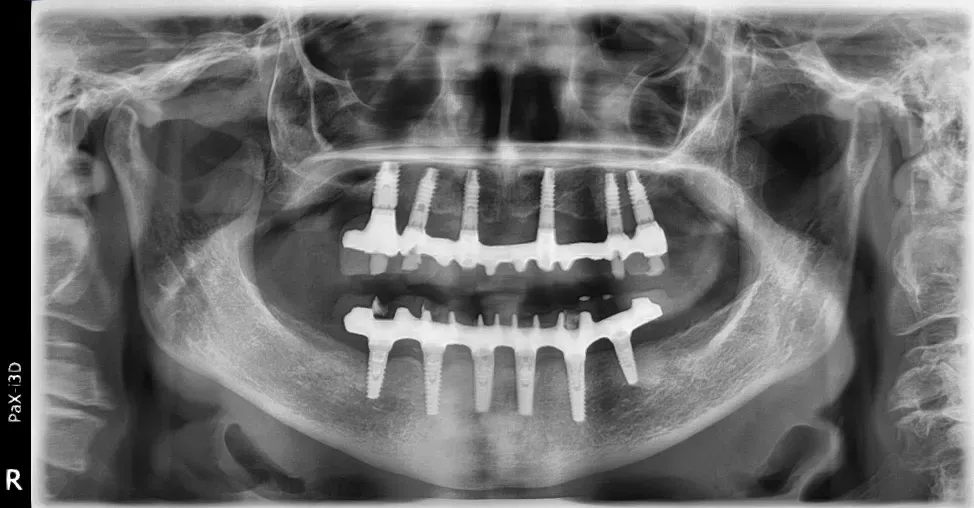

Personalmente, amo scegliere il numero e le misure degli impianti in base alle caratteristiche anatomiche del singolo paziente, piuttosto che affidarmi a protocolli troppo rigidi e standardizzati. Sempre nell’ottica della rigenerazione su misura, ritengo che ogni caso debba essere studiato individualmente per ottimizzare il risultato finale.

Le immagini radiografiche che seguono testimoniano alcune delle tante soluzioni tecniche che ho utilizzato per le arcate a carico immediato nel corso della mia carriera. Ogni caso presenta sfide diverse e richiede un approccio personalizzato.